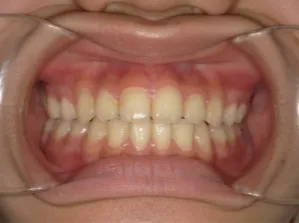

治療後⑩高2:17y7m 抜歯治療終了

口元の治療前後:15y5m→17y7m スッキリしました